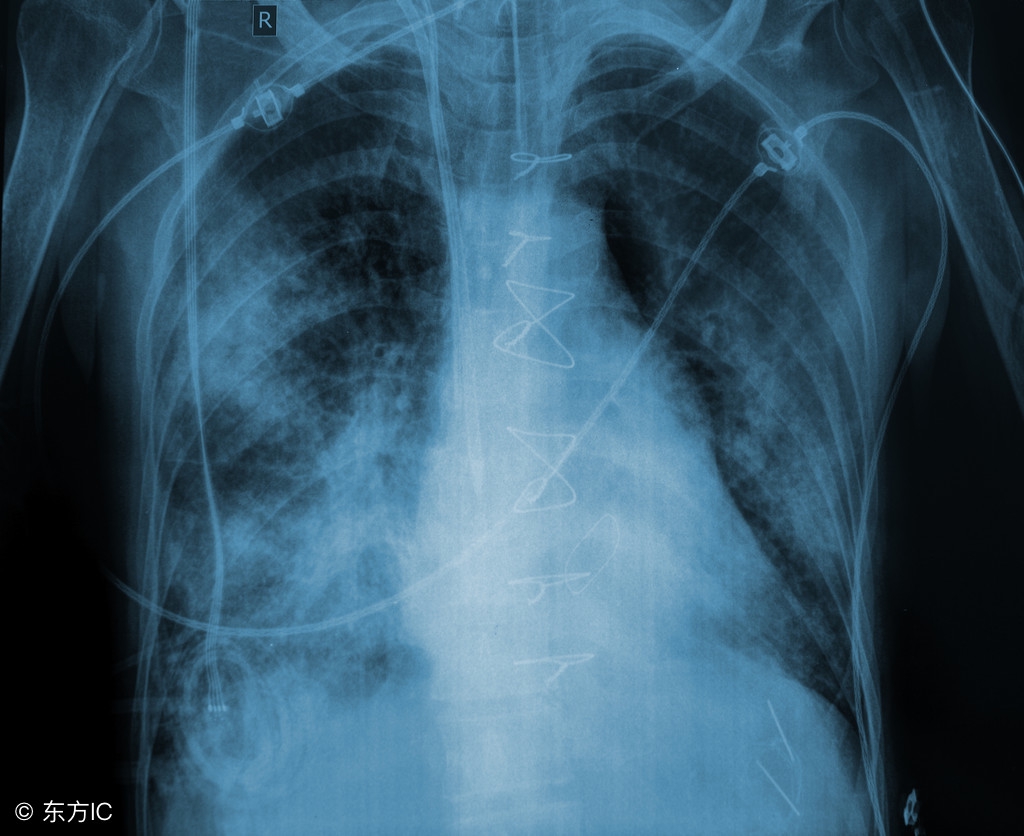

肺纹理是指胸部影像检查时看到的从肺门向肺野外围延伸的放射条状阴影,这些阴影多了即肺纹理增多

一般引起肺纹理增多的原因很多,既可以是生理性的,也可能是病理性的,常引起本症状的疾病有慢性支气管炎、支气管扩张、风心病、先心病、尘肺、癌性淋巴管炎等呼吸和心律增快、肺部罗音、肺动脉瓣第二心音亢进。胸片呈现肺部斑片状或楔状阴影,盘状肺不张一侧膈肌抬高,肺动脉增粗和局限性肺纹理减少血气分析PaO210、64kpa,肺泡氧分压与动脉血氧分压差增大;死腔/潮气量比值(VD/VT)40%;血乳酸脱氢酶450U,谷草转氨酶(AST)和肌酸磷酸激酶(CPK)正常血红素增高

胸片